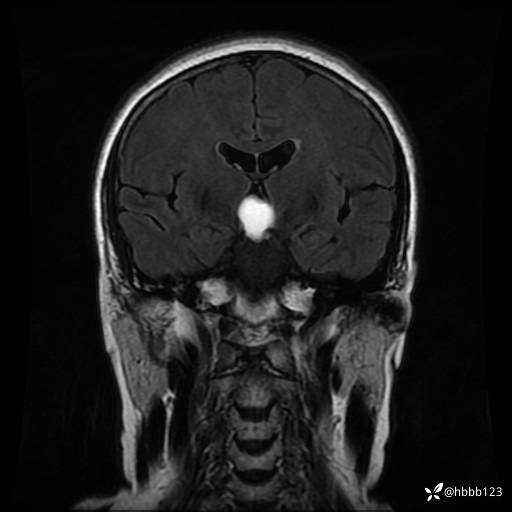

T1WI 增强 冠状位重建: